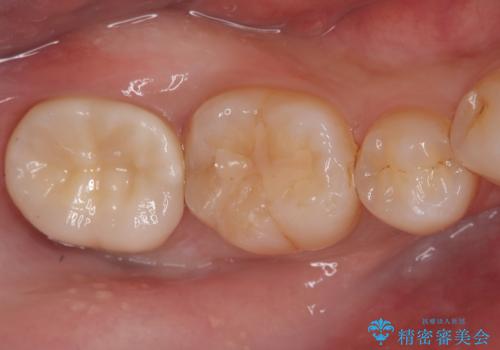

セラミッククラウンによる奥歯の修復

担当医 河口智英